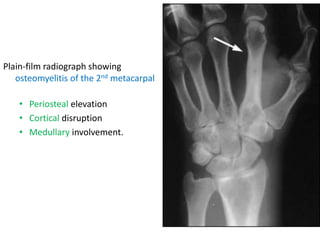

Plain-film radiograph showing

osteomyelitis of the 2nd metacarpal

• Periosteal elevation

• Cortical disruption

• Medullary involvement.